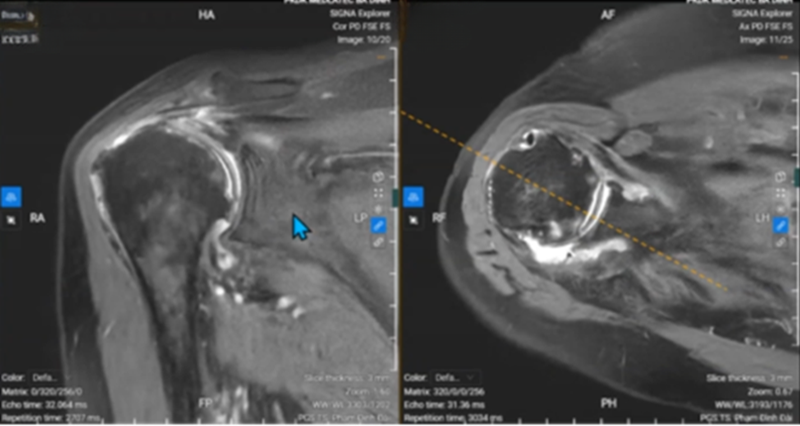

Hình ảnh chụp cộng hưởng từ cho thấy nhiều tổn thương quanh khớp vai

Kết quả cho thấy, khớp vai có nhiều tổn thương như: thoái hóa nặng mất hoàn hệ thống sụn đầu xương cánh tay, gần như là dính khớp, bong sụn viền ổ chảo, tụ dịch khớp vai, thoái hóa khớp vai.